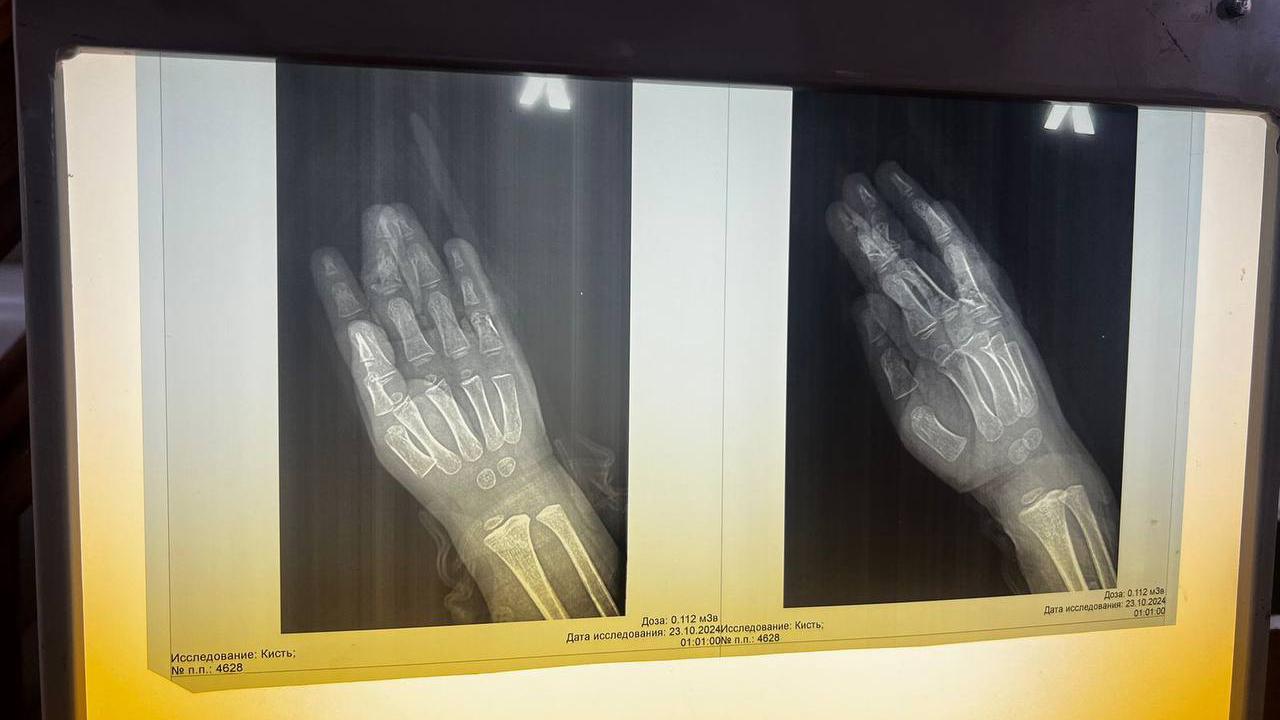

Врачи диагностировали у него открытый перелом двух пальцев со смещением. Специалисты прооперировали мальчика. Операция длилась почти четыре часа. Медикам удалось восстановить пальцы ребёнку. Кровоснабжение повреждённых тканей удовлетворительное — это значит, что они жизнеспособны. Сейчас его состояние стабильно.